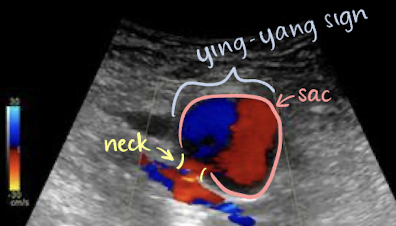

pseudoaneurysm

not lined by all 3 AO layers; blood is escaping from hole in intima layer —> outpouch and pseudo (“fake”) aneurysm

pseudoaneurysm with color Doppler

color appearance of “yin-yang” sign in sac (indicates pseudoaneurysm)

pseudoaneurysm with PW Doppler

classic “to-and-fro” Doppler signal obtained in neck of pseudoaneurysm

above baseline (positive)=blood going TO structure

below baseline (negative)=blood going AWAY from structure